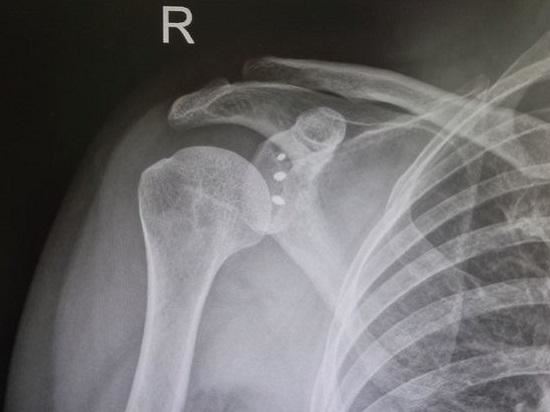

肩关节由肩胛骨的盂肱窝及肱骨头构成,又称盂肱关节,是人体活动范围最大、最具灵活性的关节。肩关节是一个典型的球窝关节,其构造犹如一个